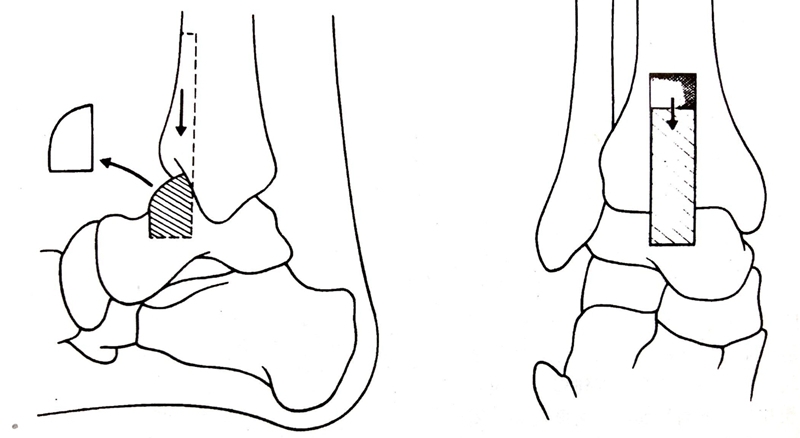

4. 从胫骨远端前侧用电锯截取一条8×2.5cm长方形骨块,在距骨颈上方做一深2cm的横行槽,将胫骨植骨块滑入槽中。

足保持在背屈度,外翻5度,外旋10度的位置上,用螺钉将植骨块近端固定到胫骨上。

通过跟骨纵向向上穿入一枚斯氏针,深度达到经骨远端3-10cm处,增加稳定性,植骨。

①将距骨后移,胫骨远端的前面与距骨头和颈的连接处在一条线上。距骨后移减少了足前方力臂的长度,使步态更接近正常。

②再通过跟骨纵行向上穿入斯氏针,达到胫骨远端上5-10cm。

③融合角度:屈曲度、外翻度-5度、外旋5-10度(胫骨结节与第一趾蹼成一直线),距骨轻度向后移位。踝功能位男性90度,女性可95-100度。

④胫骨骨瓣 10x2.5x1cm或8x2x0.8cm。